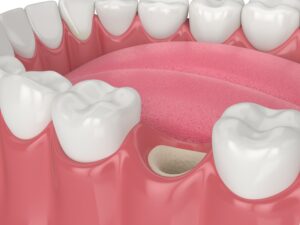

사랑니 발치를 진행하고 나면,

사랑니가 있던 자리에는

비교적 큰 구멍이 생길 수 있는데요.

이는 치아를 제거하면서

자연스럽게 형성되는 공간으로,

정상적인 치유 과정의 일부로

발치 직후에는 해당 부위에 혈액이 차오르며

혈병이라고 하는 피떡이 형성되는데,

이 혈병은 상처를 보호하고

잇몸과 뼈가 회복되는 데

중요한 역할을 하며

시간이 지나면서 이 공간은

점차 잇몸 조직과 뼈로 채워지며

서서히 아물게 됩니다.